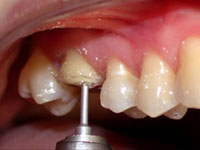

Fig. 1

Vista intra-bucal por oclusal do dente 26 mostrando as cúspides mésio-vestibular e mésio-palatina fragilizadas.

O dente 16 apresentava apenas duas cúspides remanescentes e fragilizadas, as quais precisaram ser reduzidas por desgaste (Fig. 1). Após a redução cuspídea, restou uma coroa clínica curta e com assoalho pulpar plano. Devido a essas condições não havia a possibilidade de preparar uma caixa oclusal, os degraus proximais que determinam uma cavidade MOD pois a polpa seria atingida , assim como, estrutura para reter uma coroa total. (Fig. 1, 2 e 3).

O ângulo cavo-superficial foi preparado com ponta diamantada (nº3118 da KG Sorensen) girando em baixa velocidade, formando um bisel chanfrado em toda extensão da margem vestibular e lingual do dente (Fig. 3). Por sua vez, as margens proximais foram biseladas com ponta diamantada de diâmetro menor (nº1111 da KG Sorensen) estendendo-se para vestibular e lingual com o intuito de manter o término cavitário separado do dente vizinho e manter a distância biológica horizontal (espaço para acomodar a papila sem ser comprimida, facilitar o acabamento das margens de esmalte, das bordas da restauração, a moldagem e o espaço para higienização) (Fig. 4 e 5).